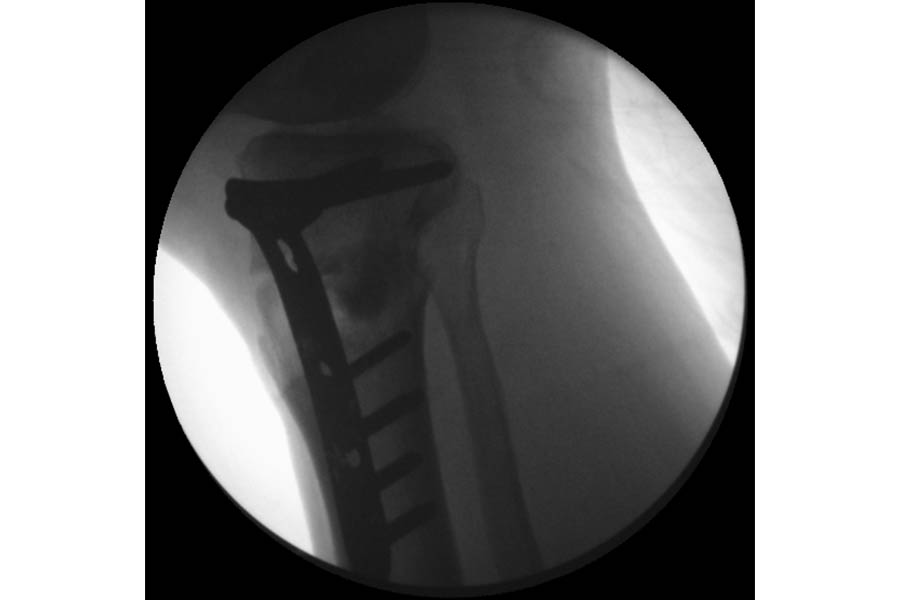

Trauma

Case 1